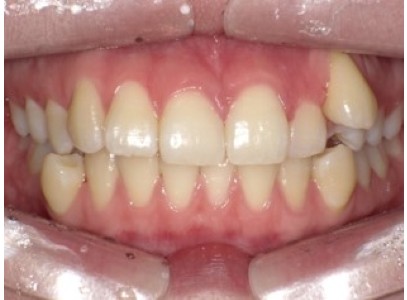

상·하악 중심선 비대칭과 2급·3급 구치관계, 비발치 교정으로 1급 교합 회복한 20대 여성 사례